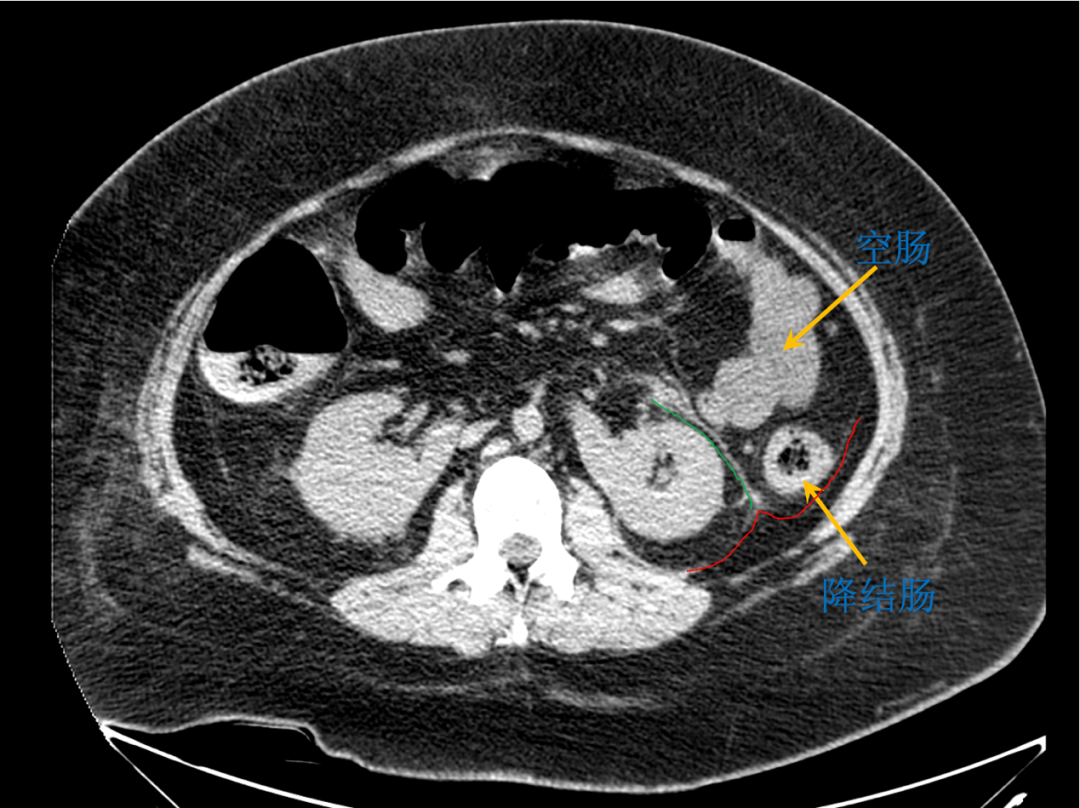

raus专栏|肾周间隙的层面与毗邻02